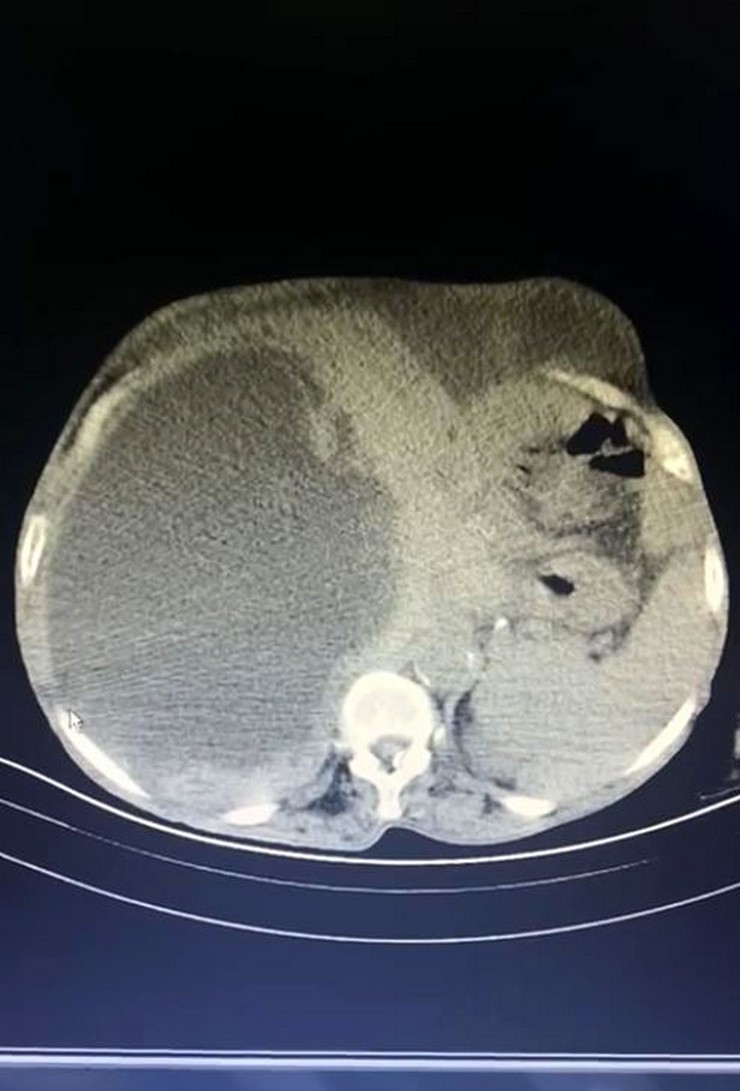

Çiftçilik yapan Asiye Taşdelen karnındaki şişlik ve ağrı nedeniyle Trabzon Kanuni Eğitim ve Araştırma Hastanesi’ne başvurdu. Taşdelen’e sağlık görevlileri tarafından yapılan muayene ve görüntüleme tetkiklerinde karaciğerinde 90 santimetreye ulaşarak karnını kaplayan 3 ayrı kedi-köpek kisti saptandı. Hasta için ameliyat kararının verilmesiyle 2 saat süren operasyon sonucunda Genel Cerrahi Uzmanı Operatör Dr. İsmet Çelik ve Gastroenteroloji Uzmanı Doç. Dr. Aydın Aktaş tarafından kistlerin 2’si çıkarılırken 1’inin içi boşaltılarak kontrol altına alındı. Dünya literatüründe 90 santimetreye ulaşarak tüm karnı dolduran bir kist ile ilk kez karşılaşıldığını ifade eden Dr. Çelik, kedi-köpek kisti olarak bilinen hastalığın bulaşma yollarını anlattı. Dr. Çelik, genellikle sokak hayvanları ile veteriner kontrolü yapılmayan evcil hayvanların dışkısıyla doğrudan temas veya dışkı bulaşan toprak, su veya yiyecekler yoluyla insan vücuduna geçen parazitlerin bu hastalığa neden olduğunu ifade etti. Dr. Çelik, kistin zamanla karaciğer, akciğer ve diğer organlara yerleşerek ciddi sağlık sorunlarına yol açabileceği konusunda uyarılarda bulundu.

Hastanın tüm karnının kistle kaplı olduğunu ifade eden Dr. Çelik, “Trabzon’da Kanuni Eğitim ve Araştırma Hastanesi bir ilke vesile oldu. Hastamız Gümüşhane’den karın şişliği ve ağrısı ile bizlere müracaat etti. Geldiğinde ileri tetkikleri yaparak, tüm karnını dolduran bir kitle ile karşılaştık. Durumu detaylandırınca kistin oluşumunu kedi ve köpekten kaynaklı olduğunu gördük. Hastamızın yandaş hastalıkları vardı. O hastalıkları ekarte edebilmek için ilgili branşlarla birlikte vakayı değerlendirdik. Hastamızın ameliyat olabilirliğini tartıştık. Konsey kararı ile ameliyatına karar verdik. Hastamızın karaciğerinde 3 ayrı kist vardı. Tüm karnı kist ile kaplıydı. 2 tanesinin tamamına çıkardık. Diğerini ise kontrole alarak içini boşalttık. Dünya literatüründe 90 santimetreye ulaşarak tüm karnı dolduran kist görmedik. Ameliyatımız 2 saat sürdü. Hastamızın safra yolları kontrol edildi. Hastamızın durumu gayet iyi. Solunum cihazından bağımsız olarak kendi başına solunum yapabiliyor. Yarın da servise alacağız” dedi.